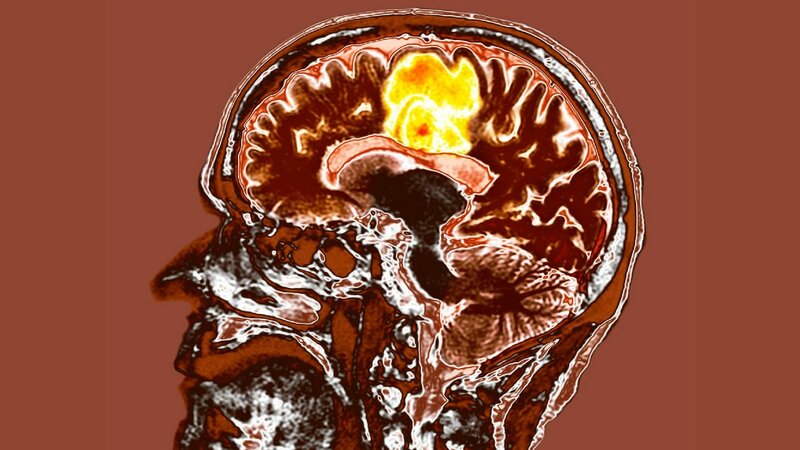

New treatment for most aggressive brain cancer may help patients live longer